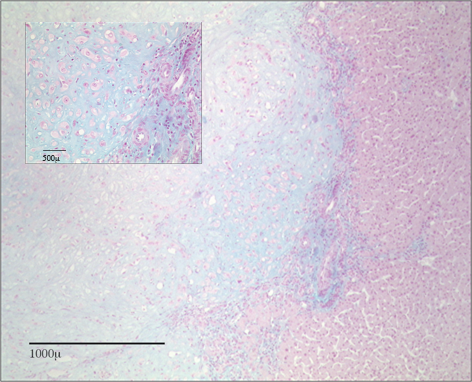

A CT scan of thorax, abdomen and pelvis confirmed a markedly enhancing mass in segment 6 of the liver, measuring about 3 cm (Figure 1 [Fig. 1]). Additional colonoscopy was without pathological findings. FNAC (fine needle aspiration cytology) was performed revealing a well-differentiated chondroid sarcoma with a proliferation index (Ki67) of 10%. Histology was confirmed by a pathology reference service. Based on the histological diagnosis a PET-CT scan and skeletal scintigraphy were undertaken revealing no pathological FDG uptake. Without evidence of any extrahepatic primary the tumor was classified as a sarcoma of hepatic origin. Comprehensive chemical and haematological laboratory did not reveal any pathologic finding. Values for AFP, CEA and CA 19-9 were within normal ranges as well. Since there were no signs of non-resectability the patient was admitted for surgery. Due to the preoperative histology of a chondroid sarcoma a right hemihepatectomy was performed in order to include the biopsy channel resulting in a 15 x 14 x 9.5 cm resection specimen. The tumor was completely resected with a distance of 1.2 cm to the resection margin and 0.9 cm to the liver surface, respectively. Macroscopically the tumor on the cut surface appeared grossly, grayish-white, measuring 3.5 x 2.7 x 2.6 cm. On (immuno-) histological examination the lesion was paucicellular revealing a substantial eosinophilic matrix (Alcian-positive) and a cartilaginous component (Figure 2 [Fig. 2]). Chondroid cells were positive for Vimentin and focally positive for S100 antigen (Figure 3 [Fig. 3]). Ki67 staining showed a proliferation index <1% (0/50 HPF), p53 was completely negative. At the margin the tumor showed remarkable proliferation of bile ducts (CK 7 positive) and interspearsed capillary vessels (CD 34 positive). Given these histologic findings molecular-cytogenetic investigations were performed to further characterise the tumor. Comparative genomic hybridisation revealed neither gain nor loss of chromosomal material. In absence of any signs of malignancy the final diagnosis of a chondroid hamartoma of the liver was made.

Figure 2: Alcian staining of the eosinophilic matrix of the tumor